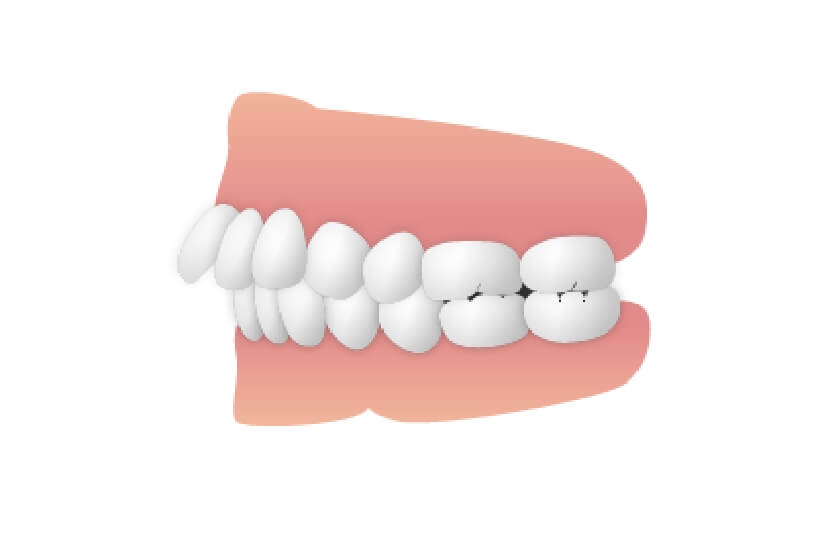

下顎前突

下顎が突き出ているケースで、いわゆる「受け口」になります。顎の成長が終わる前に治療を始める必要があり、最悪の場合、顎の骨を切断する大がかりな手術を要します。成長期であれば、「チンキャップ」と呼ばれる帽子状の器具をはめて、突出を抑えるようにします。